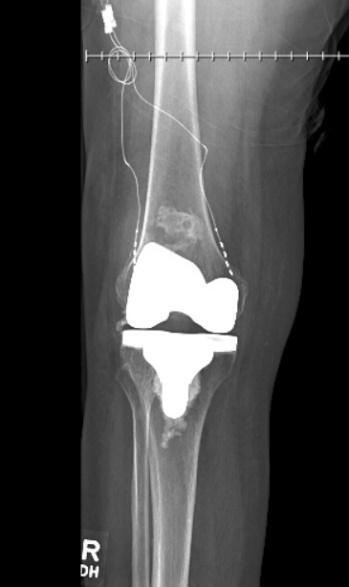

After initial evaluation by our pain management service, the patient was referred to the orthopedic surgery department for a second opinion. The orthopedic team reported her patella fracture appeared stable and given her medical comorbidities, she was deemed a non-surgical candidate. In our clinic, the patient was initiated on gabapentin 300 mg three times daily and titrated up to 1200 mg three times daily, with no improvement. She underwent genicular nerve blocks with 70% improvement. She then underwent genicular radiofrequency ablation, which produced minimal improvement. The patient was transitioned to multiple medications including topical creams, pregabalin, tramadol, hydrocodone, and oxycodone with inadequate improvement in her pain and functionality. After 6 months of failed medication changes the patient was offered a peripheral nerve stimulation trial. The decision was made to wait 6 months after the genicular RFA before proceeding with nerve stimulation to allow for nerve regeneration. Following these interventions, the patient underwent a peripheral nerve stimulation trial of the superior medial and superior lateral genicular nerves which produced 60-80% improvement therapy utilizing Nalu PNS technology [Nalu Medical, Carlsbad, California]. After the PNS trial, the patient proceeded with a long-term Nalu micro-implantable pulse generator and PNS system targeting the superior medial and lateral genicular nerves with 70% improvement. Figures below demonstrate postoperative lateral (figure 1) and anteroposterior (figure 2) X-rays. The leads were placed along the pathway of the superior medial and lateral genicular nerves which are proximal and posterior to the epicondyle of the femur.8 After permanent implantation, the patient was given a brief course of hydrocodone for postoperative pain. At her 1-month postoperative visit, she reported a 50% improvement in her pain complaints. At her 3-month postoperative visit, she had weaned off all opioid medications and was endorsing a 60% improvement in her knee pain complaints.